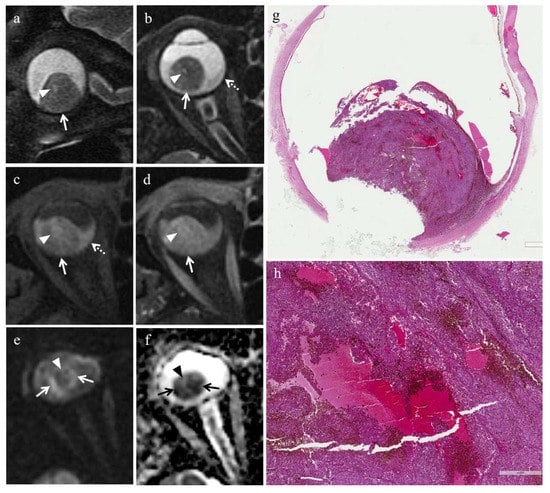

3.2.1. Histopathologic Findings in the Irradiated Group

3.3.1. MRI Findings in the Irradiated Group

| Patient | Histologic Type | Degree of Pigmentation | Degree of Necrosis | Necrotic Pattern |

|---|---|---|---|---|

| 1 | Necrosis without viable tumor tissue | - | Grade III | Sharply demarcated tumor necrosis |

| 2 | Spindle cell | Pigmented | Grade I | Sharply demarcated tumor necrosis |

| 3 | Epithelioid cell | Pigmented | Grade II | Sharply demarcated tumor necrosis |

| 4 | Spindle cell | Pigmented | Grade III | Sharply demarcated tumor necrosis |

| 5 | Mixed cell type | Poorly pigmented | Grade I | Multiple foci- hemorrhagic/coagulative-type |

| 6 | Mixed cell type | Poorly pigmented | Grade III | Sharply demarcated tumor necrosis |

| 7 | Spindle cell | Poorly pigmented | Grade III | Sharply demarcated tumor necrosis |

| MR Finding | T2 | T1 | Gd-T1 | DWI |

| Radiation-induced necrosis | ![]() Low signal | ![]() High signal | ![]() No enhancement | ![]() Low signal |

| Radiation-induced necrosis with viable tumor tissue | ![]() M RIN | ![]() M RIN | ![]() M RIN | ![]() M RIN |

| Hemorrhagic necrosis in untreated melanoma | ![]() High signal | ![]() Low signal | ![]() No enhancement | ![]() Low signal |

low signal;

high signal;

no enhancement; M: melanoma; RIN: radiation induced necrosis.| Patient | T2 | T1 | Gd-T1 | DWI | ADC × 10−3 mm2/s ** |

|---|---|---|---|---|---|

| 1 | Hypointense | Hyperintense | No enhancement | No restriction | - |

| 2 | - | - | - | - | 0.76 |

| 3 | Hypointense | Hyperintense | No enhancement | No restriction | 0.84 |

| 4 | Hypointense | Hyperintense | No enhancement | No restriction | - |

| 5 | Hyperintense | Hypointense | No enhancement | No restriction | 0.67 |

| 6 | Hypointense | Hyperintense | No enhancement | No restriction | - |

| 7 | Hypointense | Hyperintense | No enhancement | No restriction | 0.86 |